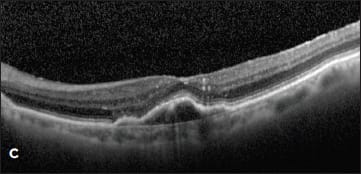

Figure 1. (top) A patient with a new occult CNV with PED and subretinal fluid was treated with two monthly intravitreal injections of ranibizumab with flattening of the PED and resolution of the SRF (bottom).

Case 1. This case involved a 92-year-old woman who presented with a new occult lesion in the left eye. Prior to her conversion, her baseline vision was 20/40. Despite new CNV with a PED and subretinal fluid noted on OCT, her vision remained unchanged (Figure 1). She was treated twice with intravitreal ranibizumab with dramatic resolution of the PED and subretinal fluid.